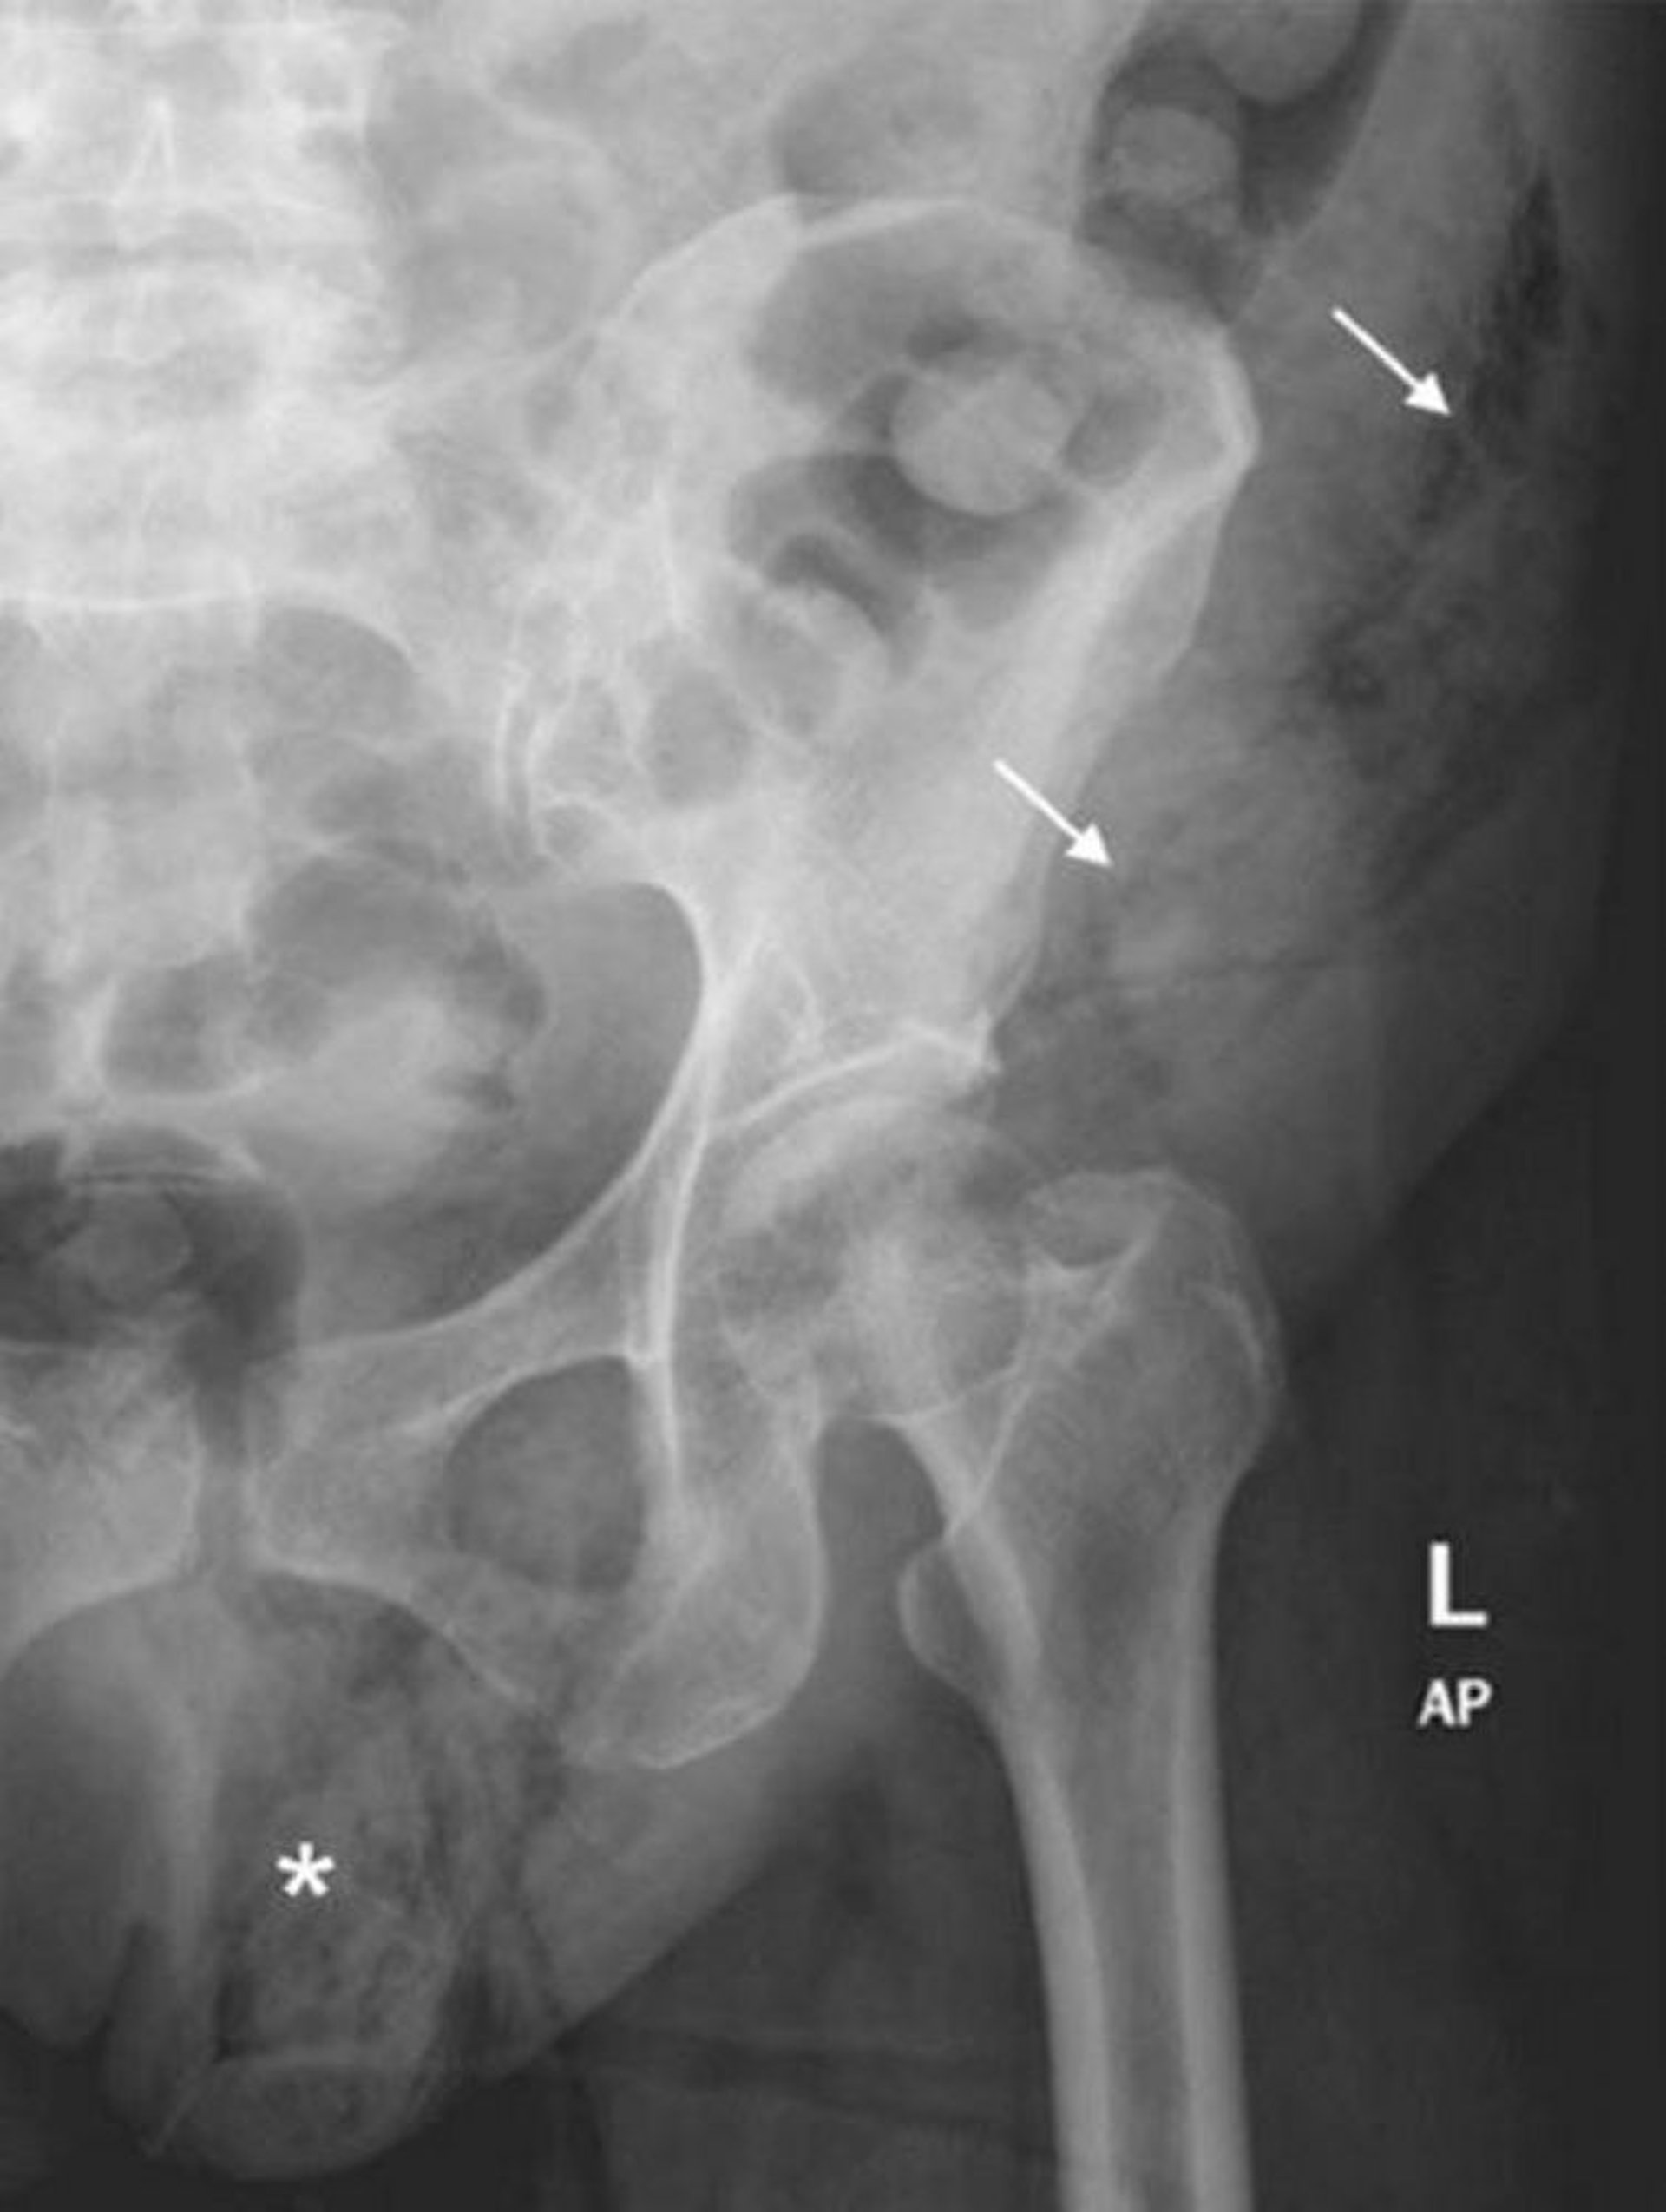

Gangrène de Fournier (radio abdominale)

Cette radiographie abdominale montre une extension des gaz des tissus mous de l'hémiscrotum gauche (*) à la paroi abdominale gauche (flèches).